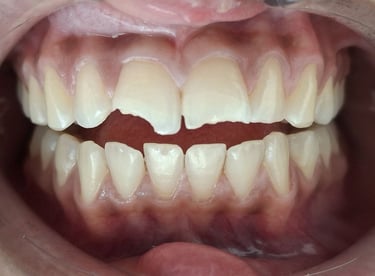

Professional Teeth Cleaning in Shyamal, Ahmedabad

Gentle, properly performed and tailored teeth cleaning for each person giving you comfort, safety and visible results. People from Shyamal and nearby areas of Ahmedabad visit our clinic for comfortable and very effective teeth cleaning.

After

All images shown here are real teeth cleaning cases treated at our clinic with patient consent.

Professional teeth cleaning helps remove plaque, tarter, and surface stains that regular at home brushing can not.

At Shree Dental Care, teeth cleaning is performed gently with focus on patient experience, comfort and long term oral health.